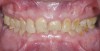

Fig 2. Preoperative frontal intraoral view in maximum intercuspation.

Figure 2

A 40-year-old patient presented with the chief complaint: “My teeth are cracking, and I would like to have my original bite.” Dental findings included Class I occlusion with slight misalignment between teeth Nos. 8 and 9. Generalized severe occlusal wear and slight Class I mobility of teeth Nos. 23 to 26 were noted. Caries lesions were found on teeth Nos. 2, 4, 6, 8, 9, and 14 and abfraction lesions on teeth Nos. 4, 5, 10, 11, 13, 20, and 21. Figure 1 through Figure 3 depict the preoperative situation. Full-mouth rehabilitation was suggested. The goals for the restorative treatment were management of erosive etiology, conservation of tooth structure, and long-term protection of the restorations. A diagnostic wax-up was instrumental in determining functional and esthetic treatment goals and establishing new anterior guidance (Figure 4). A comprehensive, step-by-step treatment approach was applied, which, after periodontal pretreatment, caries control, and provisionalization, included definitive preparation (Figure 5) and restoration of the maxillary anterior teeth to establish anterior occlusal guidance. CAD/CAM–fabricated full-contour monolithic high-translucent zirconia crowns (Katana™ UTML Ultra Translucent Multi-Layered, Kuraray Noritake Dental, kuraraynoritake.com) were fabricated (Figure 6 and Figure 7) and cemented with self-adhesive resin cement (Panavia SA, Kuraray Noritake Dental). Figure 8 demonstrates the cemented anterior crowns and refined conservative preparations of posterior teeth, which were performed with minimal tooth-structure removal. High-translucent monolithic zirconia onlays and crowns were fabricated (Katana Zirconia UT, Kuraray Noritake Dental) (Figure 9 to Figure 12). The posterior restorations were adhesively bonded following the APC zirconia-bonding concept. APC-Step A involved air-particle abrasion with 50-μm aluminum oxide at 1.5 bar with a chairside microetcher (Figure 13), followed by application (APC-Step P, Figure 14) of a special ceramic primer (ClearfilTM Ceramic Primer, Kuraray Noritake) with adhesive phosophate monomers (MDP). Relative moisture and contamination control was achieved with cotton rolls and retraction cords. Rubber dam placement, which is always preferred, was difficult in this situation. The enamel surfaces of the abutment teeth were selectively etched (Figure 15) with 35% phosphoric acid (K-Etchant Gel, Kuraray Noritake Dental) and the dentin conditioned (Figure 16) with a self-etch dentin primer (Panavia V5 Tooth Primer, Kuraray Noritake Dental). A dual-cure adhesive resin (Panavia V5 Paste Universal, Kuraray Noritake Dental) was dispensed directly into the restorations with an automix syringe. The restorations were inserted, and excess cement was carefully removed (Figure 17 and Figure 18) before light polymerization (Figure 19). Postoperative views depict the treatment outcome (Figure 20 to Figure 22).